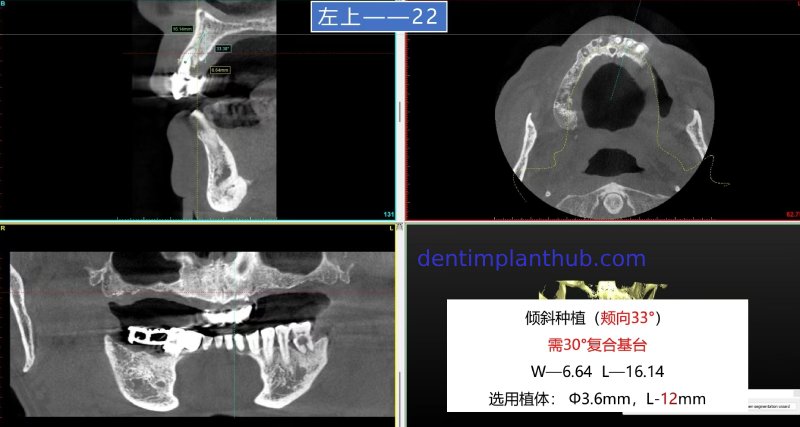

For tooth 22, with a width of 6.64 and a height of 16.14, an implant with a diameter of 3.6 and a length of 12 is selected. It needs to be implanted at an inclination. The buccal angle is 33°, and a 30° composite abutment is required.